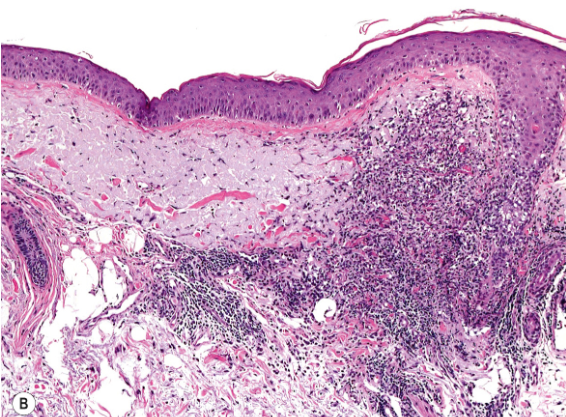

Q

What do you see here

A

Nodular granulomatous infiltrate composed of histiocytes, histiocytioc giant cells and admixed lymphocytes in upper interfollicular dermis